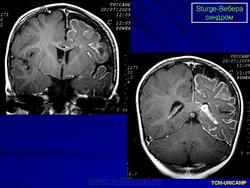

Магнитная резонансная томография пациента с болезнью Штурге - Вебера

Магнитная резонансная томография пациента с болезнью Штурге - Вебера